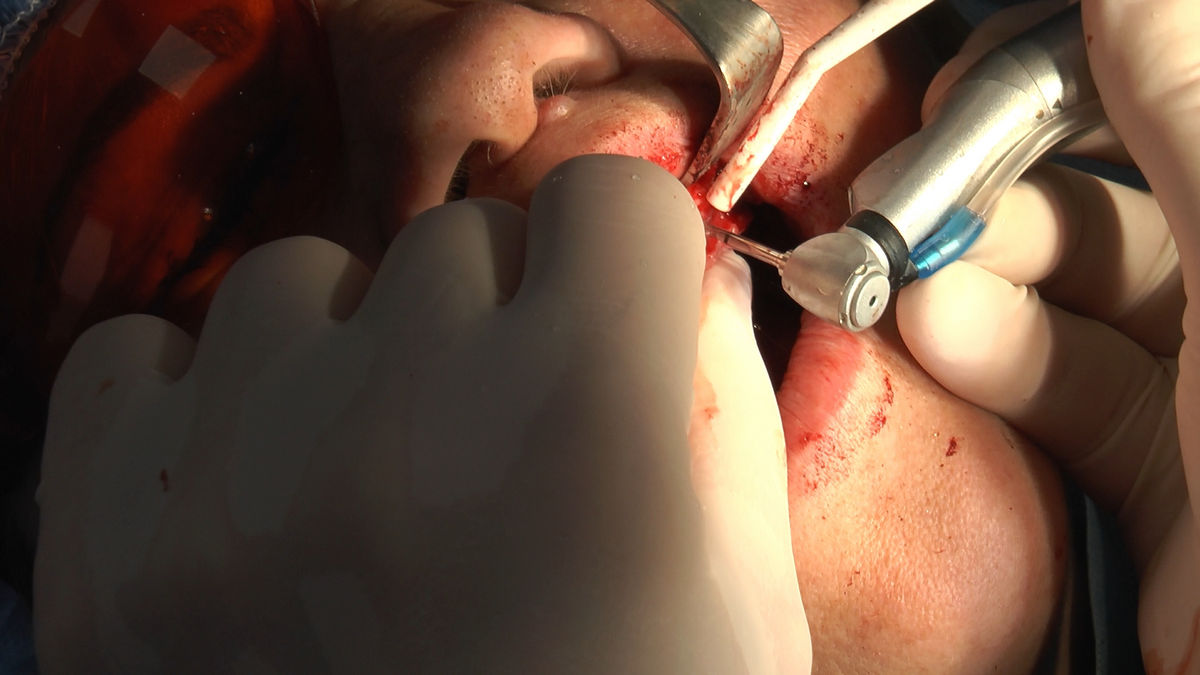

Practiculum Implantologii – Sezon VI, sesja 3, część 1